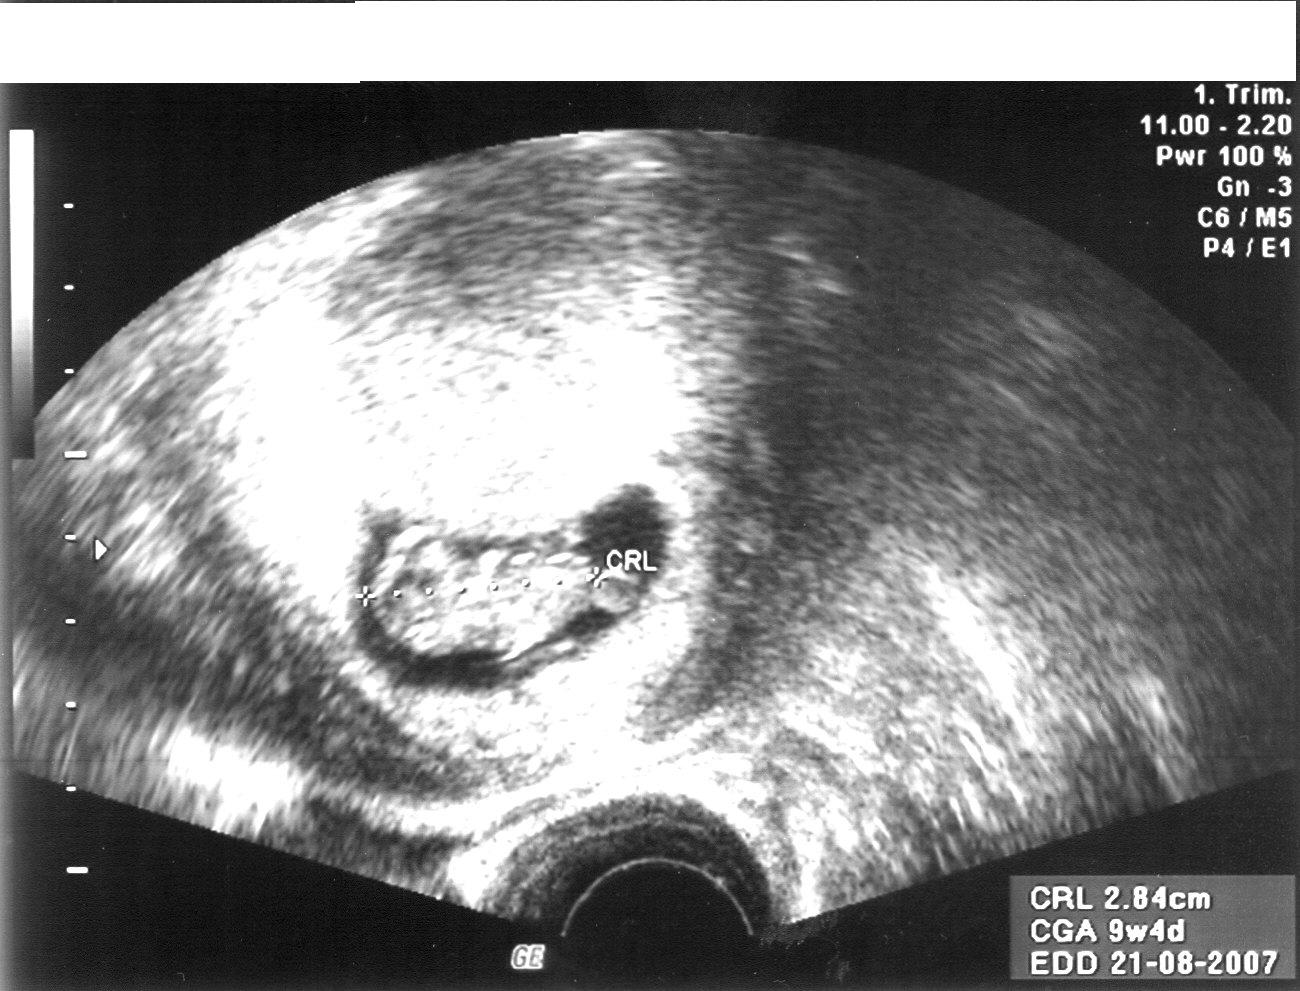

Ähm,Spritzen...noch 4 mal Progesteron, und bis einschl. 12. SSW Leukonorm wöchentlich,und dann in der 14. und in der 16. SSW . Dann habe fertig...und mache ein großes Kreuz!!!